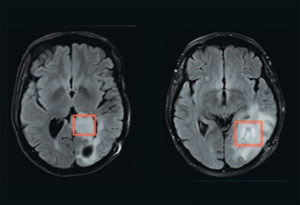

The new imaging technique uses magnetic resonance (MR) spectroscopy, which analyses the magnetic properties of atomic nuclei, to locate 2-HG in the brain. Other researchers have tried to image 2-HG with MR spectroscopy, but found it difficult to distinguish 2-HG from some of the brain's common metabolites, such as glutamate and glutamine.

MGH researchers led by George Sorensen and Ovidiu Andronesi, the lead author of the Science Translational Medicine paper, found a way to unambiguously detect 2-HG by doing the MR scans in two dimensions, which gives enough information to conclusively distinguish 2-HG from similar compounds. The imaging technique does not require any specialised equipment; it can be done with the clinical MRI scanners already found in most hospitals.